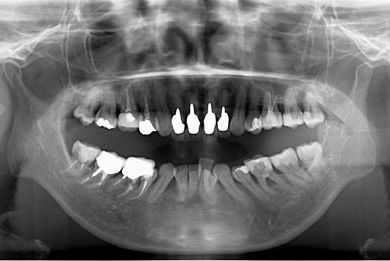

| 性別/年齢 | 女性 / 40歳 | ||||||||||||||||||||||||||||||||

| 主訴 | 前歯のつけ根の黒い部分を見えないようにしたい。 | ||||||||||||||||||||||||||||||||

| 治療方針 | 上顎前歯をセラミック治療にて審美的回復を行う。 | ||||||||||||||||||||||||||||||||

| 治療内容 | オールセラミッククラウン4本(セラミック用土台4本) | ||||||||||||||||||||||||||||||||